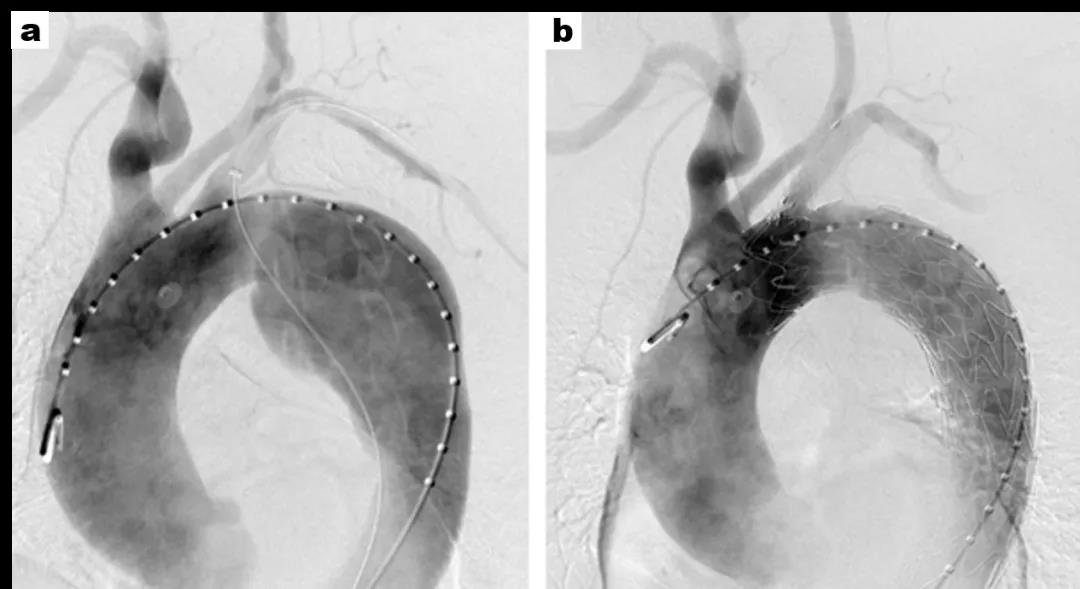

术前(a)夹层动脉瘤显著累及弓部

术后(b)夹层动脉瘤被齐全断绝